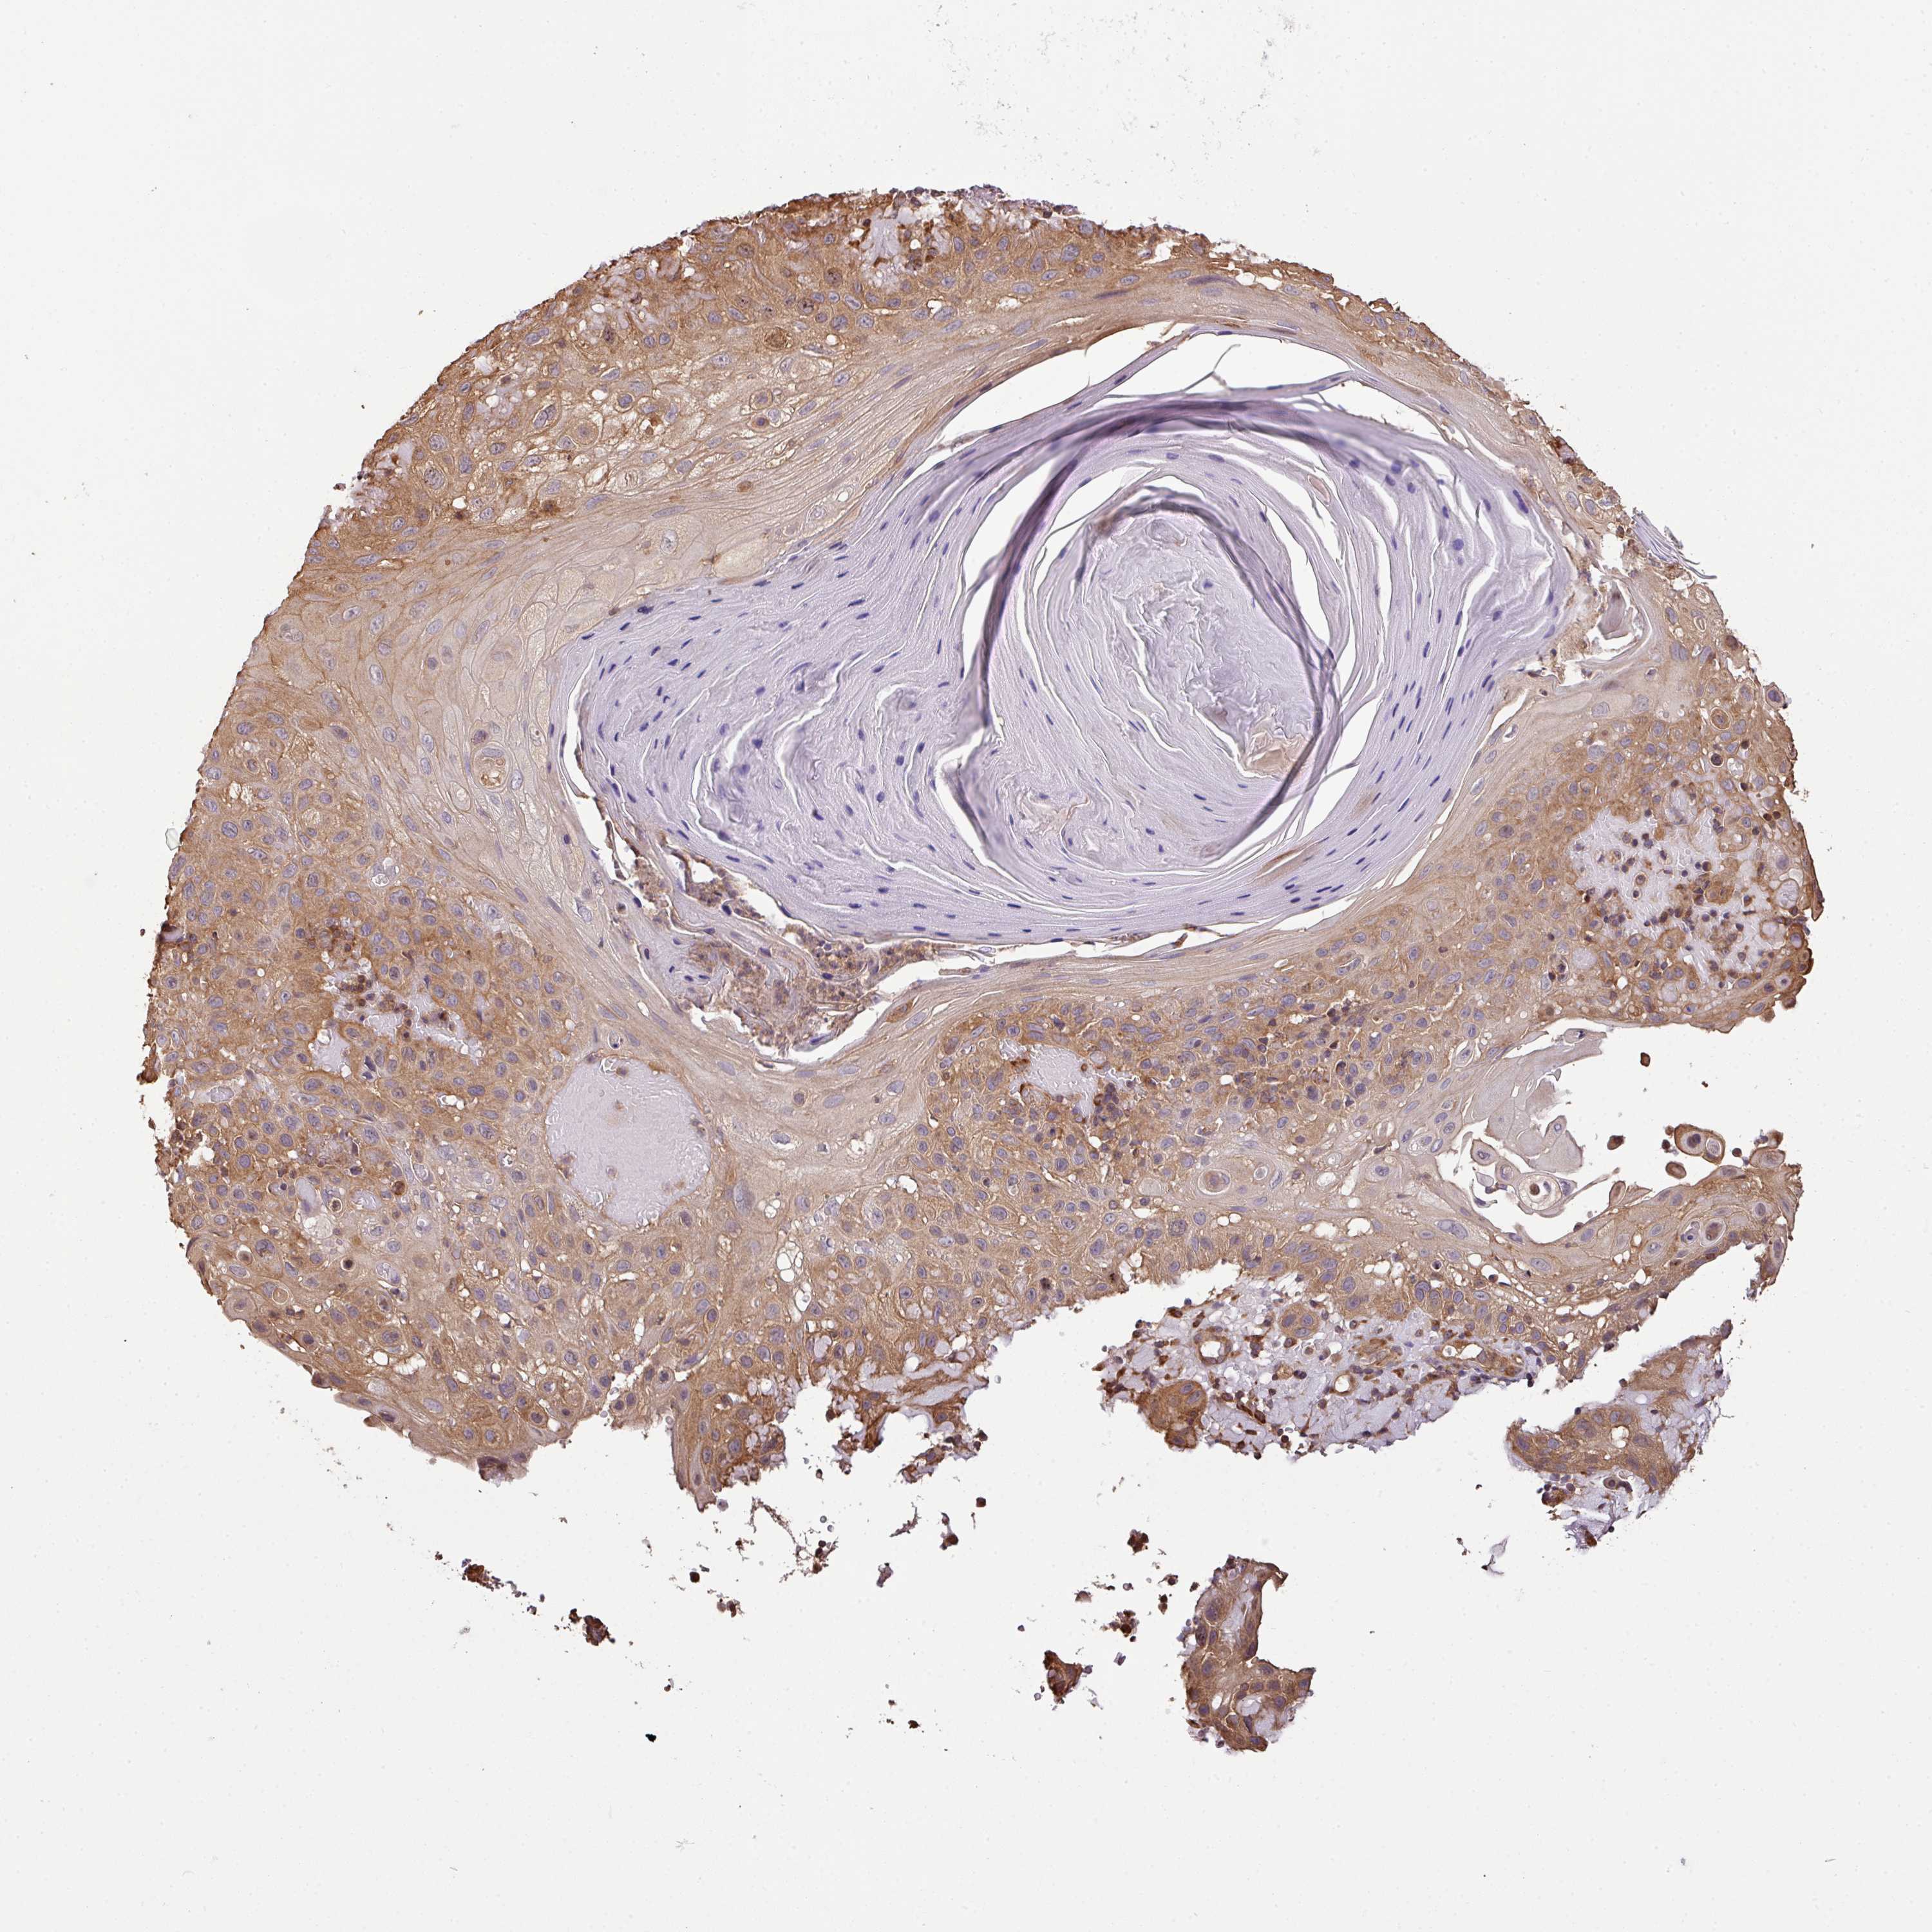

Basal cell and squamous cell cancer

SKIN CANCER - Protein expressioni

A mouse-over function shows sample information and annotation data. Click on an image to view it in a full screen mode. Samples can be filtered based on level of antibody staining by selecting one or several of the following categories: high, medium, low and not detected. The assay and annotation is described here.

Each image is clickable and will lead to virtual microscopy that enables deeper exploration of all samples and also displays staining intensity scores, fraction scores and subcellular localization as well as patient and tissue information for each sample.

Antibody HPA050955

Staining

High

Strong

Moderate

Quantity

>75%

Location

Nuclear

Cytoplasmic/membranous

Basal cell carcinoma

Squamous cell carcinoma, NOS

Squamous cell carcinoma, metastatic, NOS